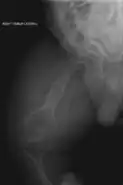

Diagnosis is typically based on medical imaging, including plain X-rays, and symptoms. In severe OI, signs on medical imaging include abnormalities in all extremities and in the spine.[97] As X-rays are often insensitive to the comparatively smaller bone density loss associated with type I OI, DEXA scans may be needed.[5]: 1514

An OI diagnosis can be confirmed through DNA or collagen protein analysis, but in many cases, the occurrence of bone fractures with little trauma and the presence of other clinical features such as blue sclerae are sufficient for a diagnosis. A skin biopsy can be performed to determine the structure and quantity of type I collagen. While DNA testing can confirm the diagnosis, it cannot absolutely exclude it because not all mutations causing OI are yet known and/or tested for.[83]: 491–492 OI type II is often diagnosed by ultrasound during pregnancy, where already multiple fractures and other characteristic features may be visible. Relative to control, OI cortical bone shows increased porosity, canal diameter, and connectivity in micro-computed tomography.[98] OI can also be detected before birth by using an in vitro genetic testing technique such as amniocentresis.[99]